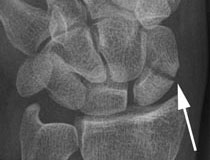

Die Diagnosestellung eines Kahnbeinbruchs ist gelegentlich nicht einfach. Sehr wichtig sind die genaue Beschreibung des Unfallmechanismus und eine sorgfältige klinische Untersuchung. Aufgrund der schrägen Lage des Kahnbeines in der Handwurzel ist auf einer Standard-Handgelenksaufnahme der Bruch nicht immer sicher darstellbar. Unverschobene Brüche können deshalb nicht eindeutig darstellbar sein. In solchen Fällen ist eine Spezialaufnahme (Kahnbein-Serienaufnahme) sinnvoll. Bei anhaltenden Beschwerden und negativem Röntgenbefund sollte nach etwa 2 Wochen einen erneute Röntgenkontrolle durchgeführt werden, da nach dieser Zeit durch die eintretenden Resorptionsvorgänge der Bruchspalt besser zu sehen ist. In Zweifelsfällen kann eine Computertomographie oder in Ausnahmefällen eine Kernspintomographie erfolgen. Wenn ein Bruch nachgewiesen ist, ist zur besseren Beurteilung in der Regel eine Computertomographie empfehlenswert. Bei der Computertomographie ist wichtig, dass die Untersuchung in sehr dünnen Schichten (Multislice Geräte) erfolgt, um die Fraktur eindeutig darstellen zu können.